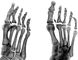

В первой стадии субхондрального асептического некроза отмечают небольшое уплотнение структуры костной ткани одной из головок плюсневых костей. Вторая стадия характеризуется уплощением суставной поверхности головки и увеличением плотности ее костной ткани (рис. 2, а). Степень деформации головки плюсневой кости может быть различной: от небольшого выпрямления суставной поверхности до значительного уменьшения высоты головки. В этот период отчетливо определяется расширение суставной щели смежного плюсне-фалангового сустава. Третья стадия — стадия рассасывания некротической костной ткани — рентгенологически проявляется в виде фрагментации головки плюсневой кости (рис. 2, б). Форма, величина и плотность фрагментов различны. Контуры их неровные, зазубренные или подчеркнуто четкие. Суставная щель остается расширенной. Вслед за рассасыванием некротических масс следует репарация костной ткани — четвертая стадия. Фрагменты исчезают, и восстанавливается однородный рисунок структуры деформированной головки. Головка плюсневой кости приобретает блюдцеобразную форму с углублением в центре и выступающими в сторону краями. В результате уплощения головки укорачивается плюсневая кость. Суставная щель суживается и имеет неравномерную ширину. Исходом остеохондропатии головок плюсневых костей является развитие деформирующего артроза — пятая стадия (рис. 2, в). Вдоль деформированной головки плюсневой кости возникают гребневидные и бахромчатые костные разрастания. В этот период особенно отчетливо определяется деформация смежной поверхности основной фаланги за счет уплощения ее основания и краевых костных разрастаний.